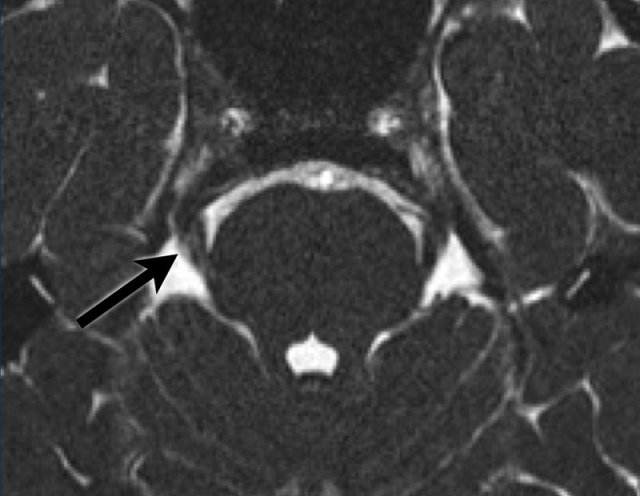

A 45 year-old female with a history of pain on the right side of the mandible, alleviated by extraction of multiple dental elements.

However, since one month, she is experiencing the same type of pain once more. The pain is sharp and radiates from the chin, via the right side of the face to the skull. The pain is evoked by talking, eating, and touching the right sides of the face.

3D FIESTA shows a lesion in Meckel’s cave, hyperintense on DWI, hypo-intense on ADC (not shown), extending into the cisternal segment.

This lesion is suspicious for an epidermoid.